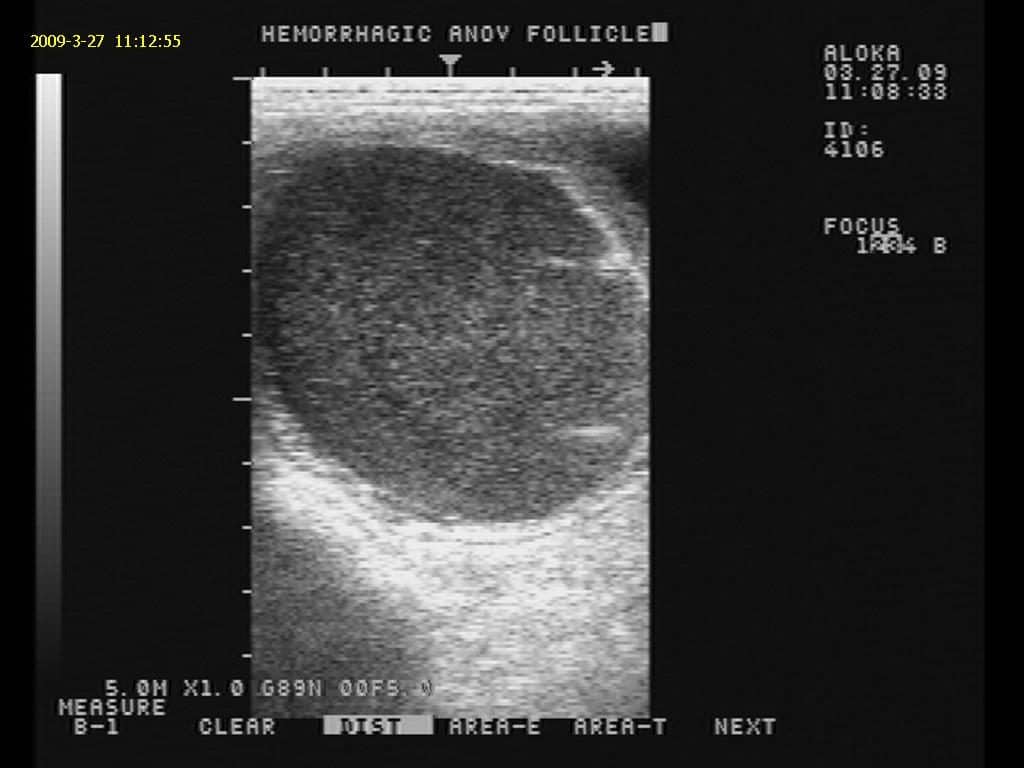

Mares in Heat: What’s Normal, What’s Not?

Mares get a bad rap for recalcitrant estrous behavior, but hormones and tumors could also be at play.

Here’s a look at the ordinary, as well as not so ordinary, ovarian abnormalities you might encounter in your broodmares.

Knowing which ovarian abnormalities are benign and which are pathogenic can help vets manage mare successfully.